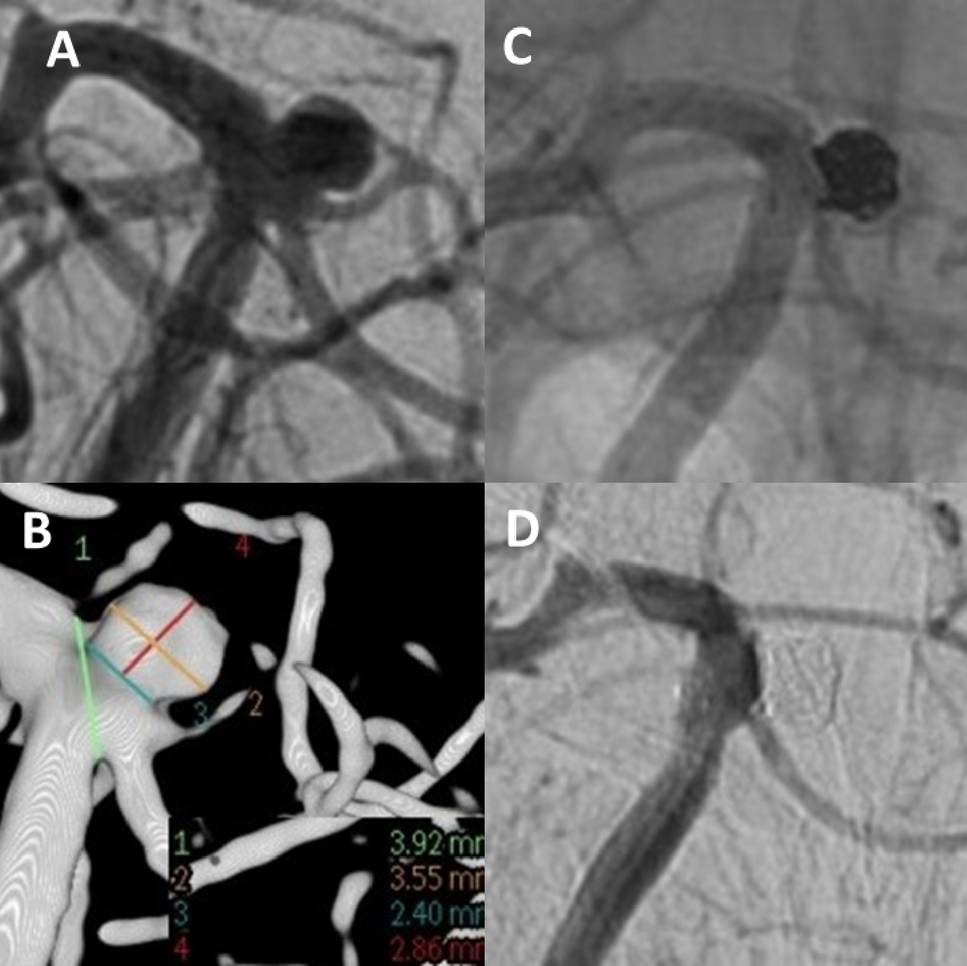

Figure 2

Unruptured aneurysm at the basilar tip (A + B). Stent-assisted coiling was intended. A stent (barrel-3550) with a barrel-shaped central segment was inserted to bridge the aneurysm neck in such a way that both the aneurysm base and the doubled superior cerebellar artery on the left are secured. The aneurysm sac is then probed through the stent mesh with a SL10-MC and closed with a total of 6 platinum micro-spirals. (C) Two-years angiographic control shows complete aneurysm occlusion (D).